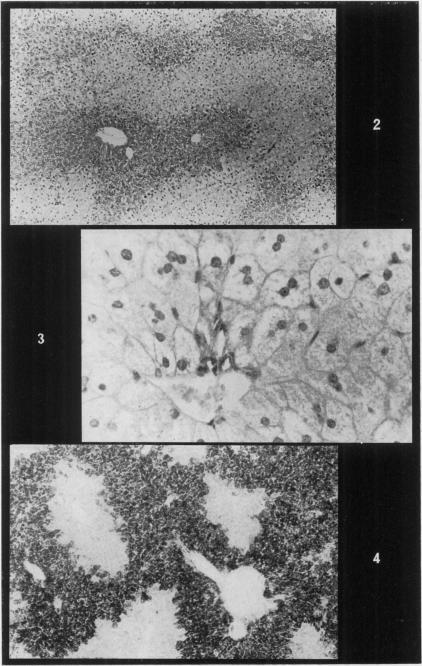

Coxsackie B3 virus injected into mice on the eighth day of pregnancy resulted in foetal wastage and growth retardation. Although in apparent good health, the pregnant animals ate more food than the controls yet failed to increase in body weight as normal. This observation, together with the maternal autopsy findings of pancreatic acinar atrophy and hepatitis, suggests that the animals are subject to a manifestation of dietary deficiency attributable to an inability to break down and digest protein in their diet. It would seem that whilst the possibility of the virus exerting a direct effect on the foetuses cannot be ignored, the action of the virus in reducing the state of health of the pregnant mother is largely responsible for the foetal effects seen.

在怀孕第8天给小鼠注射柯萨奇B3病毒会导致胎儿流产和生长发育迟缓。尽管怀孕的动物表面上健康状况良好,但它们比对照组吃更多的食物,却未能像正常情况那样增加体重。这一观察结果,连同胰腺腺泡萎缩和肝炎的母体尸检结果,表明这些动物出现了饮食缺乏的表现,这是由于它们无法分解和消化饮食中的蛋白质所致。似乎虽然不能忽视病毒对胎儿产生直接影响的可能性,但病毒降低怀孕母亲健康状况的作用在很大程度上导致了所观察到的胎儿影响。